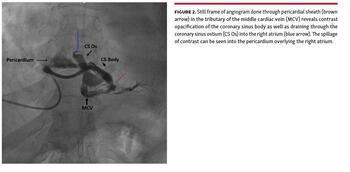

A 52-year-old woman presented to another hospital with progressive dyspnea of 10-day duration. The patient was diagnosed with a massive pericardial effusion and underwent pericardiocentesis. However, the patient’s symptoms did not improve and she was referred to our hospital with a pericardial sheath in situ. On evaluation, the patient had a large pericardial effusion and evidence of cardiac tamponade, but no fluid could be aspirated from the sheath. We attempted intrapericardial placement of a guidewire through the sheath to allow the insertion of a pigtail catheter. A 0.035˝ J-tipped Terumo wire was inserted, and it coursed through the right ventricle into the right atrium and inferior vena cava (Figure 1). Angiogram (Video 1) showed the sheath to be communicating with a tributary of the middle cardiac vein with contrast opacification of the coronary sinus and right atrium (Figure 2), and spillage of dye into the pericardium. The patient underwent surgical exploration. The sheath was inside the pericardial cavity; however, no damage was observed to the right ventricle or coronary venous system. The exact communication could not be documented as the sheath was likely pulled into the pericardial space during manipulation. The guidewire likely passed through one of the tributaries of the middle cardiac vein connected to the thebesian veins that drained directly into the right ventricle, as can be seen from the course of the wire (Figure 1). The patient was diagnosed to have pericardial tuberculosis and treated with antitubercular therapy. She was discharged and is doing well on follow-up. The current case underscores the importance of image-guided pericardiocentesis.